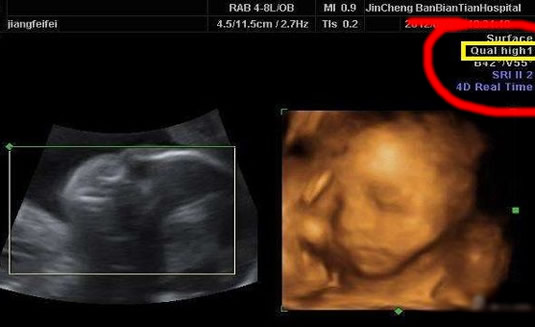

四维彩超high1和high2是不能看男女的,四维彩超右上角的high1和high2主要是代表了超声检查仪的质量,所以和胎儿性别其实并没有什么关系。...

1.四维彩超high1和high2是不能看男女的,四维彩超右上角的high1和high2主要是代表了超声检查仪的质量,所以和胎儿性别其实并没有什么关系。

按照英语翻译来看:四维彩超high1和high2一般出现在四维彩超检查报告单上,代表高质量的意思,1和2分别代表了两种不同等级的超声检查仪的质量。其原因是对超声机图像质量高低的等级的设置,以便于适合不同身体状况的孕妇进行产检,孕妇可不用过多关注这方面的信息,而这种数值与男孩女孩没有任何关系,所以在四维彩超单上出现这两个数据的时候也不要随便和孩子是男是女扯上关系,因为这本就是一个简单的数据标识,没有实在的意义。

3.根据仪器的工作状态变化:high1和high2其实也分别代表了两种不同等级的超声检查仪的质量,如果四维彩超的工作状态非常好,报告单上就会显示high1,如果工作状态一般就会显示high2。